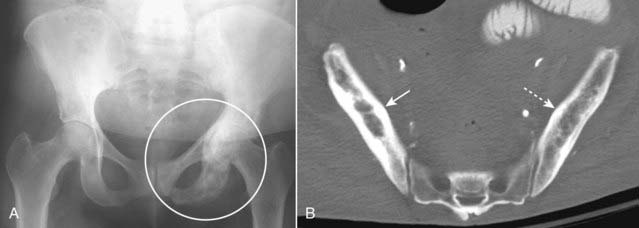

Figure 21-12 Paget disease of the pelvis, two patients.

A, A frontal view of the pelvis shows an increase in bony density in the left hemipelvis, accentuation and coarsening of the trabeculae, and thickening of the cortex (white circle), the hallmarks of Paget disease of bone. Compare the left hemipelvis with the normal right side. B, Axial CT scan of the pelvis of another patient with Paget disease demonstrates thickening of the cortex and accentuation of the trabeculae in the right ilium (solid white arrow). Compare it with the normal left side (dotted white arrow).